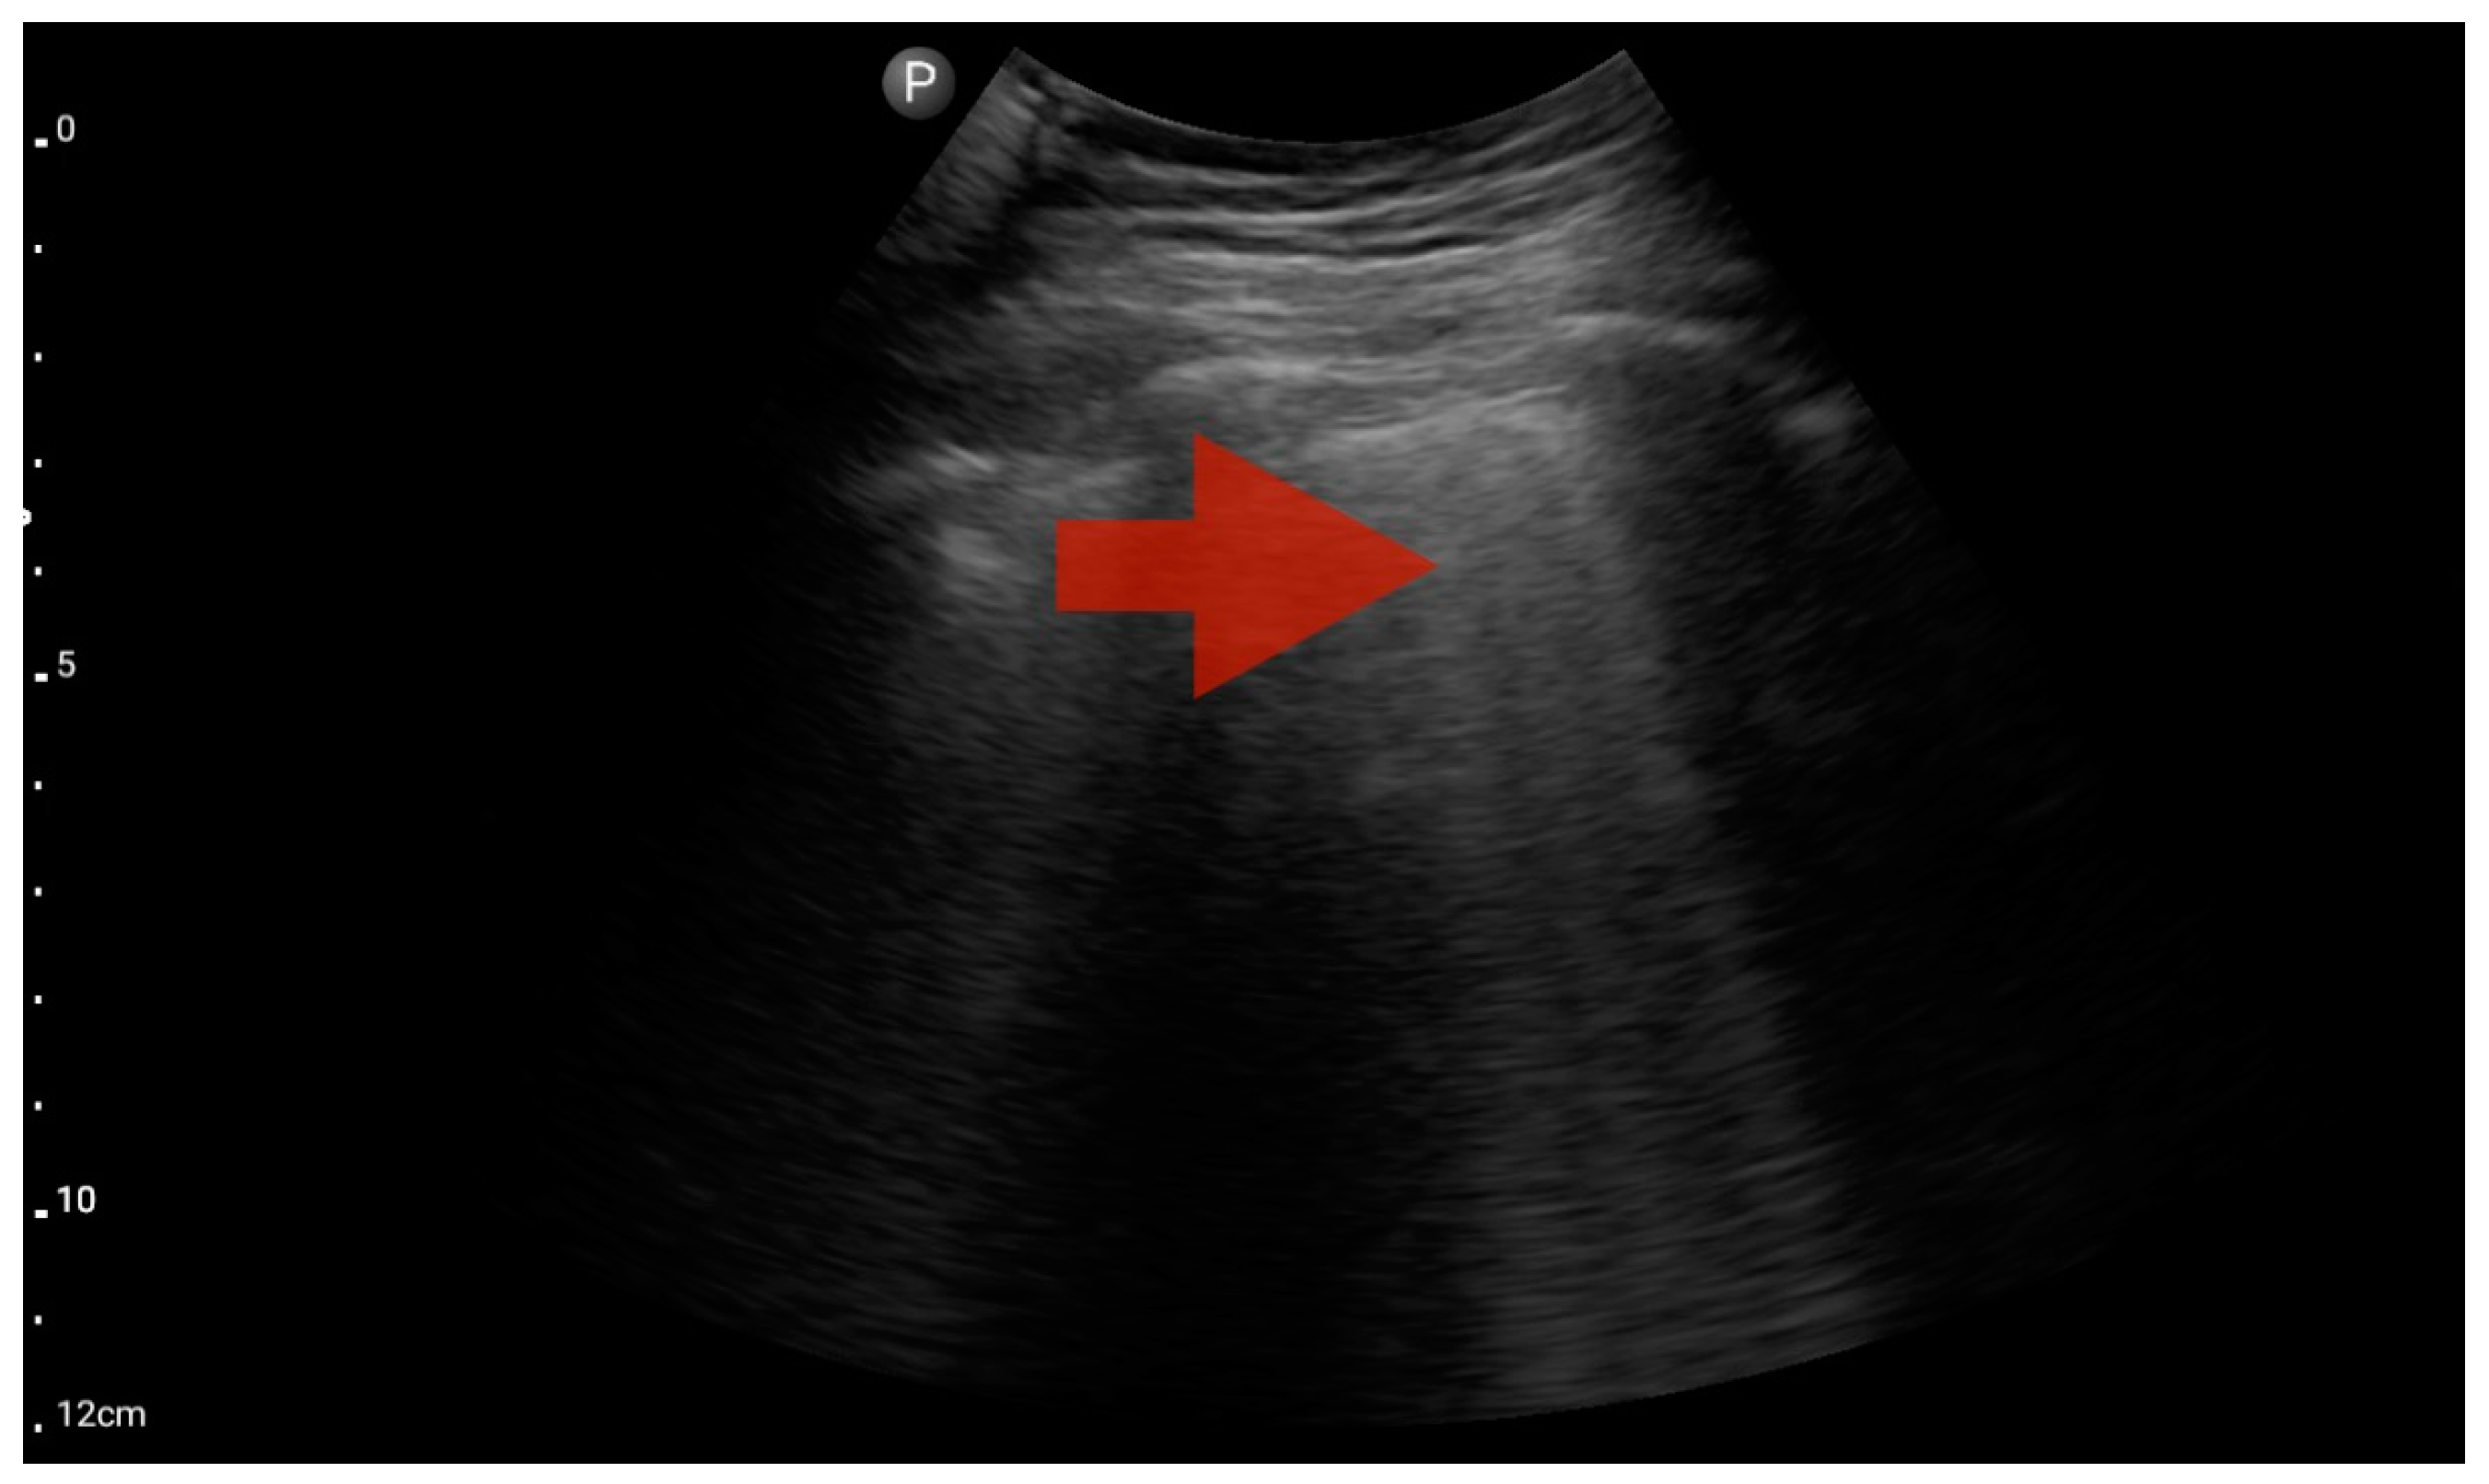

Figure 11.

Pleural effusion (BLUE protocol). Convex probe examination, the basal part of the lung (pleural recess); the red arrow indicates free fluid in the pleural cavity (source: author’s material—DK).